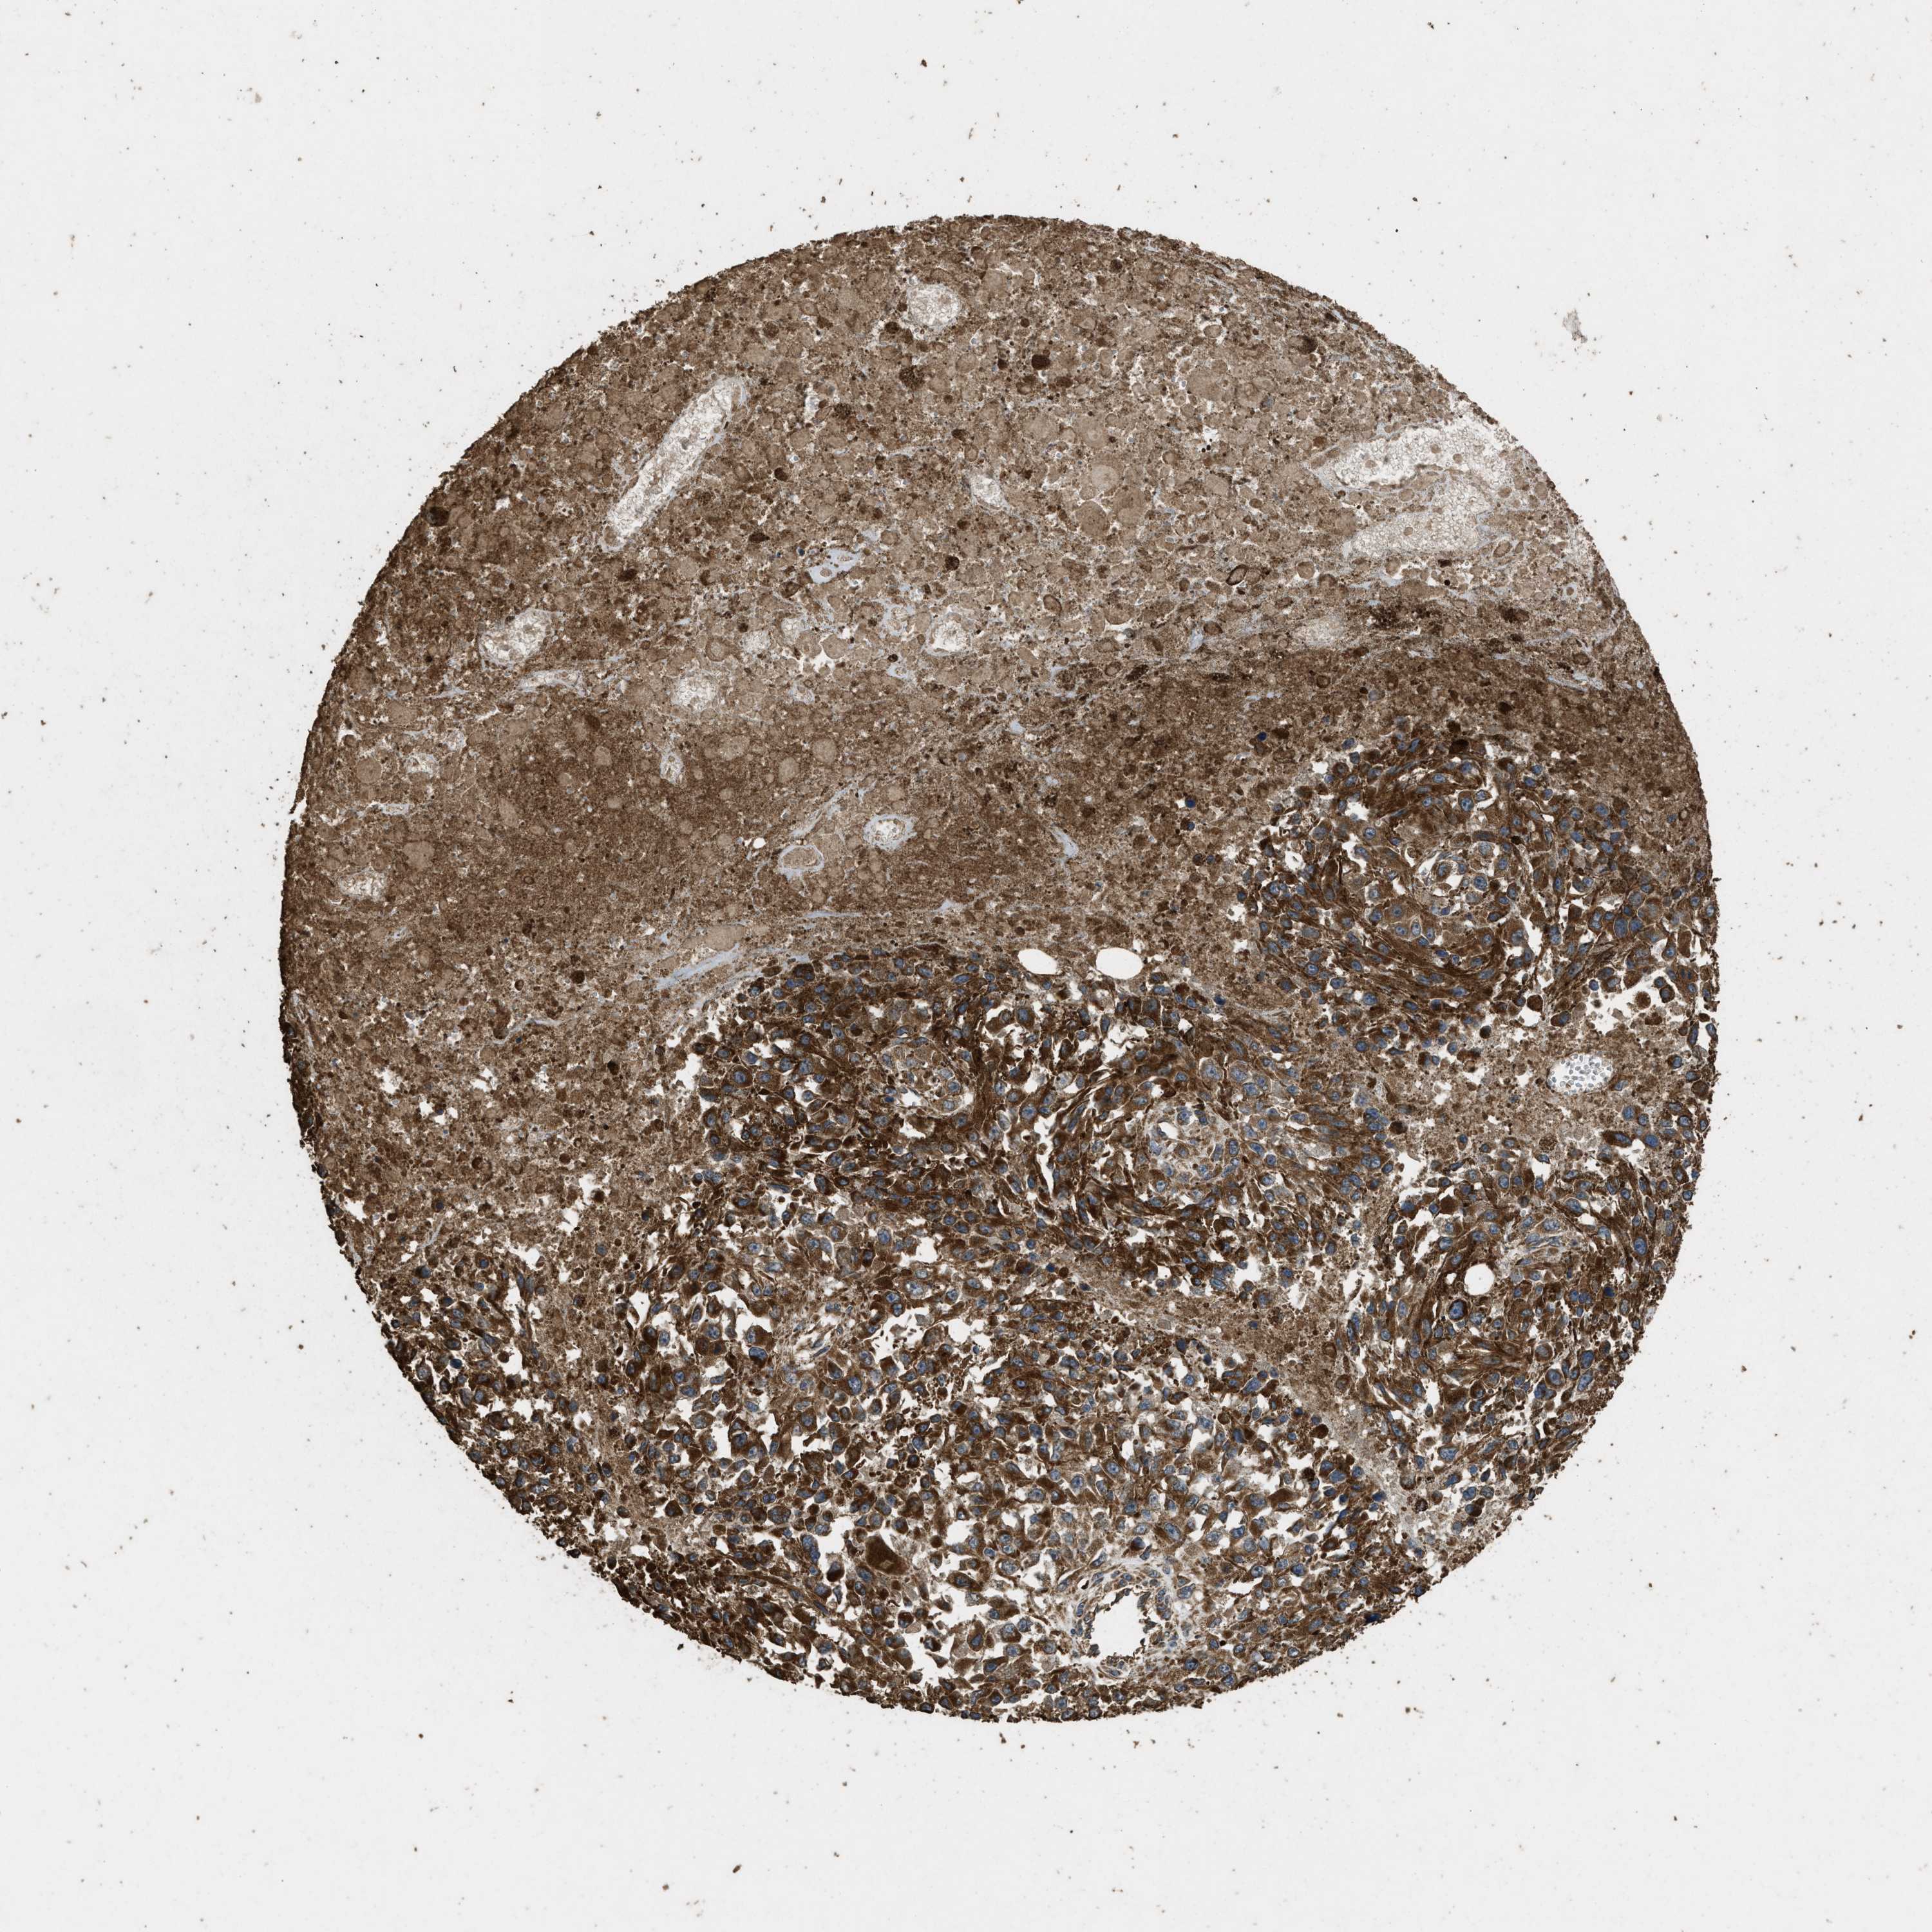

MELANOMA - Protein expressioni

A mouse-over function shows sample information and annotation data. Click on an image to view it in a full screen mode. Samples can be filtered based on level of antibody staining by selecting one or several of the following categories: high, medium, low and not detected. The assay and annotation is described here.

Note that samples used for immunohistochemistry by the Human Protein Atlas do not correspond to samples in the TCGA dataset.

Antibody stainingi

Antibody staining in the annotated cell types in the current human tissue is reported as not detected, low, medium, or high, based on conventional immunohistochemistry profiling in selected tissues. This score is based on the combination of the staining intensity and fraction of stained cells.

Each image is clickable and will lead to virtual microscopy that enables deeper exploration of all samples and also displays staining intensity scores, fraction scores and subcellular localization as well as patient and tissue information for each sample.

Antibody CAB017847

Staining

High

Medium

Low

Not detected

Intensity

Strong

Moderate

Weak

Negative

Quantity

>75%

75%-25%

<25%

None

Location

Nuclear

Cytoplasmic/membranous

Cytoplasmic/membranous,nuclear

Malignant melanoma, NOS

Malignant melanoma, Metastatic site